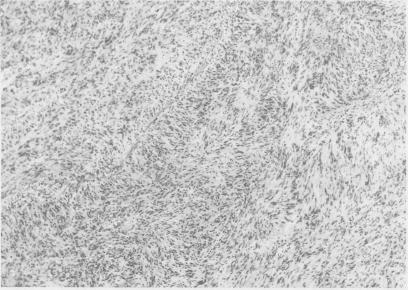

We report a patient with a jejunal leiomyosarcoma who presented with fever of unknown origin. Resection of the tumour resulted in resolution of his symptoms.